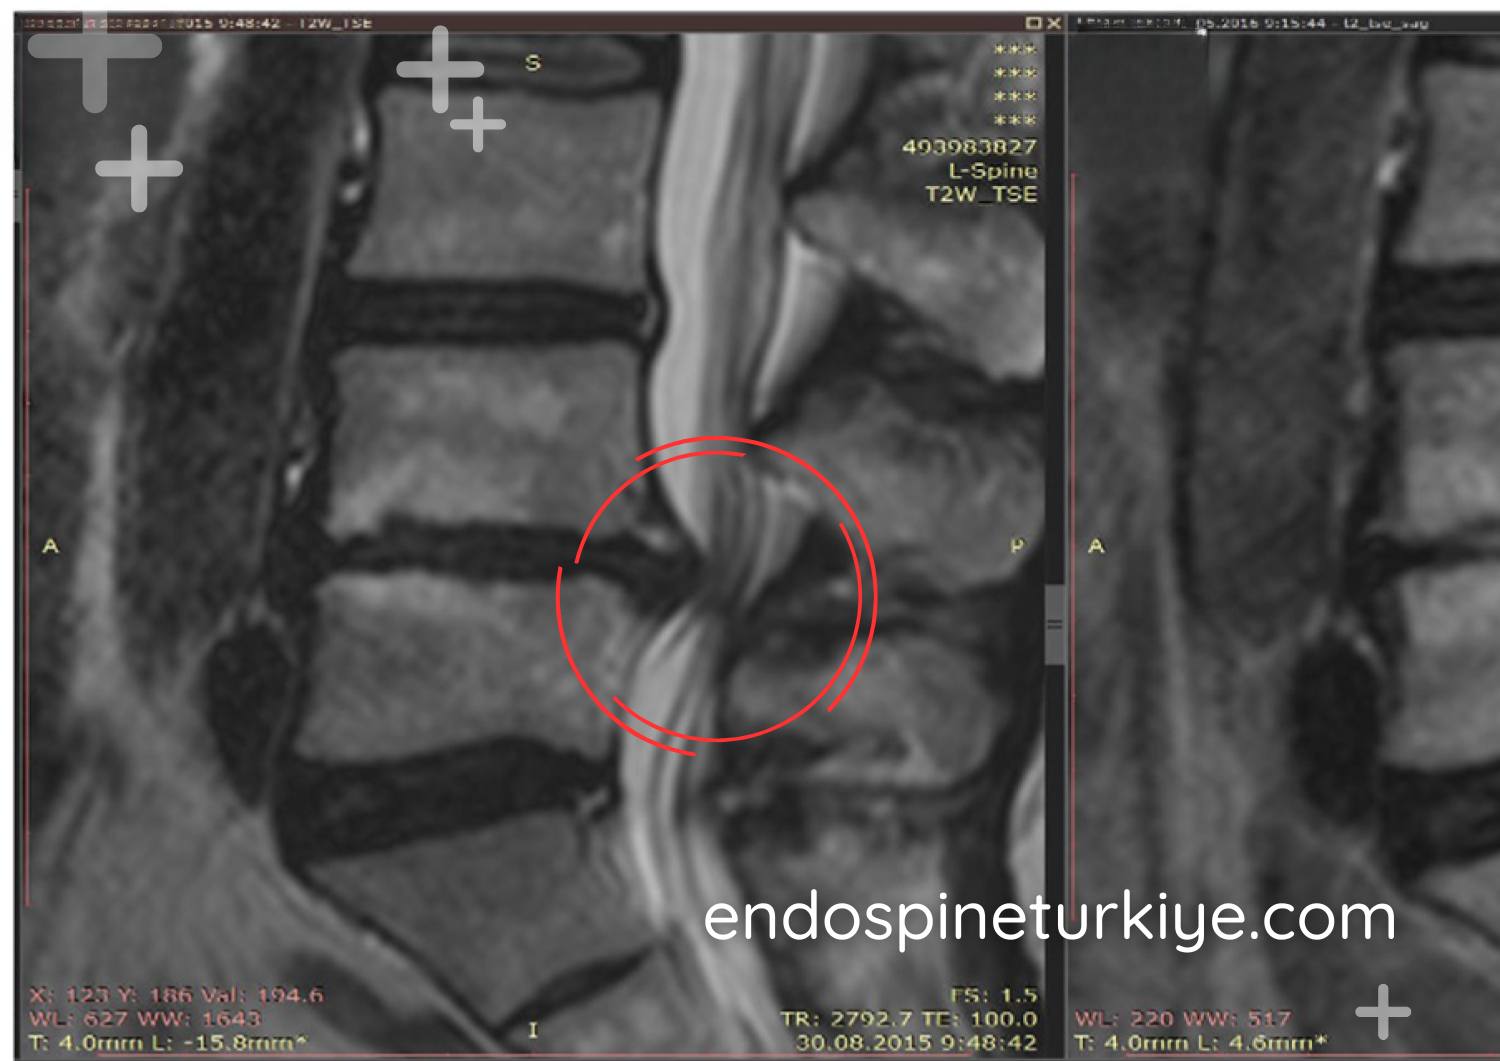

Bel Fıtığı Ameliyatı Öncesi ve Sonrası

Tedavi Öncesi

Tedavi Öncesi

MR görüntülerinde endoskopik bel fıtığı ameliyatı öncesi ve sonrası karşılaştırma